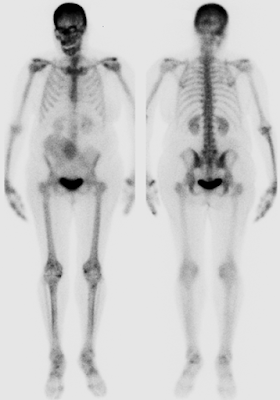

3. To assess for skeletal metastases as part of the staging workup, a whole-body bone scintigraphy was performed.

Quiz 1

1. Which of the following findings is most significant on a bone scan?

(1) Radiotracer uptake in both shoulders

(2) Radiotracer uptake in the sacroiliac joints

(3) Soft tissue radiotracer uptake in the right lower abdomen

(4) Radiotracer uptake in both kidneys

Explanation:

In bone scintigraphy using Tc-99m MDP, radiotracer uptake typically reflects areas of increased osteoblastic activity and bone turnover.

• Uptake in the shoulders (1), sacroiliac joints (2), and kidneys (4) is often physiologic or nonspecific.

• However, extraosseous uptake in soft tissue, as seen in (3), is abnormal and clinically significant.

In this case, the soft tissue uptake in the right lower abdomen corresponded to a calcified uterine leiomyoma, which may mimic metastatic lesions and requires careful differential diagnosis.

2. In this patient, is skull uptake associated with osteoblastic metastasis?

(1) True

(2) False

The increased radiotracer uptake in the skull was due to frontal hyperostosis, specifically hyperostosis frontalis interna, a benign overgrowth of the inner table of the frontal bone.

• It is commonly seen in elderly women and is not related to metastatic disease.

• Misinterpreting this benign variant could lead to overdiagnosis of metastasis.

2. What does the right lower quadrant radiotracer uptake on the anterior projection of the whole-body bone scintigraphy most likely represent?

(1) Metastatic breast cancer

(2) Large calcified uterine fibroid

(3) External contamination

Whole-body bone scintigraphy with Tc-99m MDP usually highlights areas of increased osteoblastic activity. Occasionally, it also localizes to extraosseous calcifications, including dystrophic calcifications in soft tissues.

• In this case, the right lower quadrant uptake correlates with the location of the large calcified uterine leiomyoma seen on CT, confirming a benign etiology.

• Metastatic breast cancer (1) typically results in uptake in osseous structures, not soft tissue masses in the pelvis.

• External contamination (3) would present as irregular, superficial, or streaky activity without anatomical correlation on CT.

This case illustrates an important pitfall in bone scan interpretation — extraosseous tracer uptake, which, if not correctly identified, could be mistaken for metastatic disease.

🩻 Imaging Findings:

• Whole-body bone scintigraphy shows no evidence of osteoblastic metastatic disease.

• There is focal radiotracer uptake in the right lower abdomen, corresponding to a large calcified uterine fibroid (confirmed on CT).

• Additional findings include radiotracer uptake in bilateral shoulders and sacroiliac joints, consistent with degenerative joint disease.

• Frontal hyperostosis is also noted on the skull, representing a benign variant.

Diagnosis:

• No skeletal metastases

• Incidental calcified uterine leiomyoma mimicking osseous or soft tissue metastatic uptake

• Degenerative changes in multiple joints

• Frontal hyperostosis interna (benign)

Contrast-enhanced abdominal and pelvic CT demonstrates marked uterine enlargement due to multiple calcified fibroids, with the uterus extending cranially into the right lower abdomen.